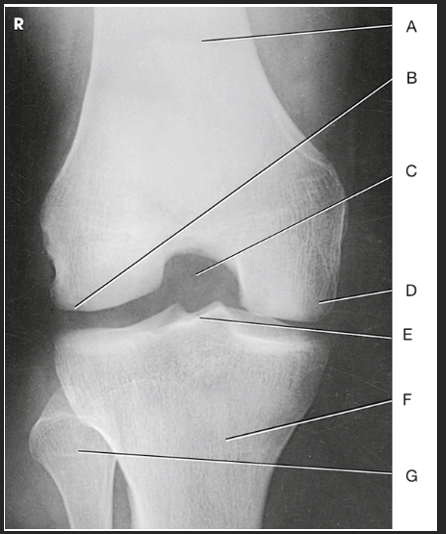

Name this projection

AP knee

Where does the CR enter for this projection?

½" inferior to patellar apex

If the patient is sthenic (19-24 cm) how is the CR directed?

0 degrees (perpendicular to IR)

Label the image: A

femur

Label the image: B

patella

Label the image: C

lateral femoral epicondyle

Label the image: D

lateral femoral condyle

Label the image: E

Lateral tibial plateau

Label the image: F

intercondylar eminence

Label the image: G

head of fibula

Label the image: H

tibia

Label the image: I

fibula